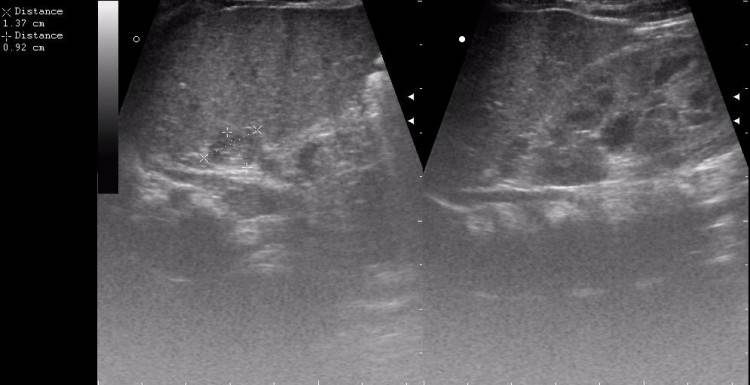

image

Как правило, диагностировать опухоль в надпочечниках удается только тогда, когда ее размеры достигают 2 см. Это связано не столько с недостатками диагностики, сколько с поздним обращением с жалобами — на начальных стадиях опухоль просто не ощущается и может быть выявлена разве что в процессе планового обследования

Доброкачественные образования – аденома и альдостерома – образуются на коре надпочечников. Это гомогенные (однородные) образования в среднем 4-5 см. с четкими краями и низкой эхогенностью. В случае обнаружения опухоли делают заключение об очаговом образовании в проекции надпочечников. Получение вывода о заболевании дает основание для подготовки и проведения дальнейших обследований.